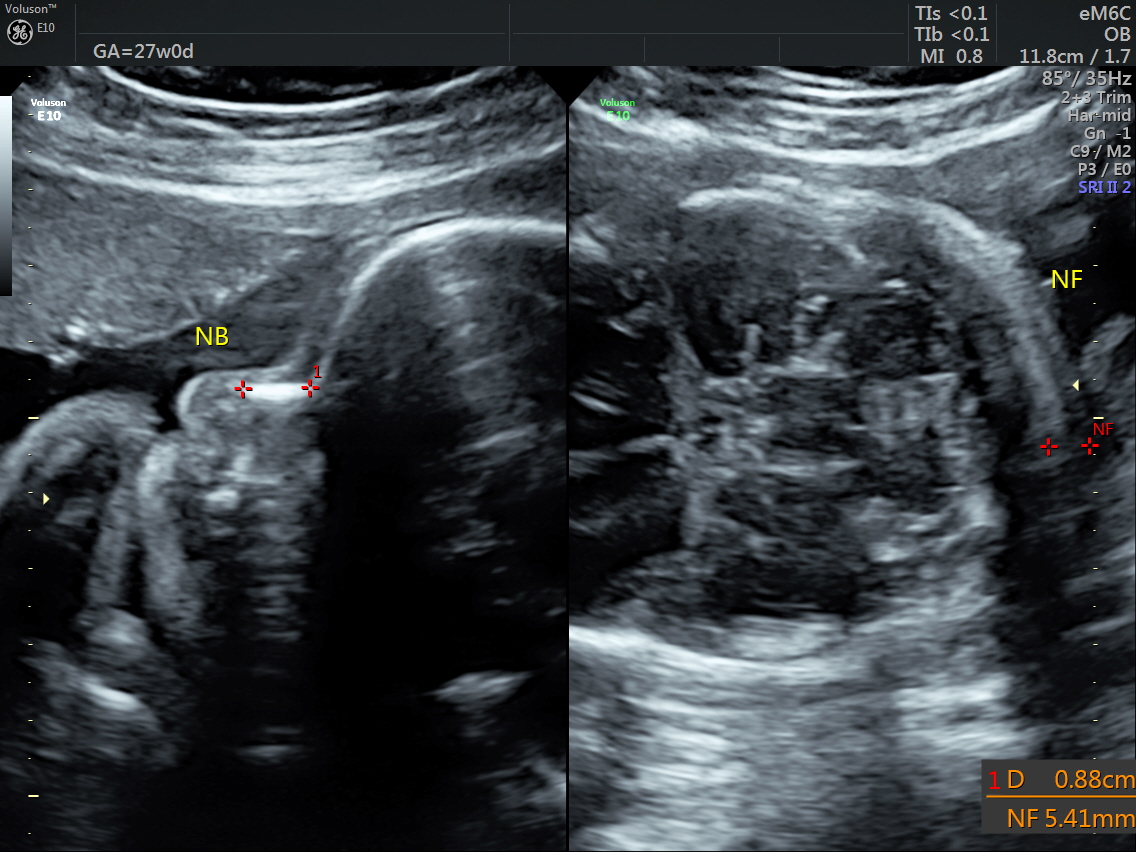

RT AORTIC ARCH_7 Published June 17, 2016 at 1136 × 852 in Rt aortic arch and aberrant left subclavian artery ← Previous Next →